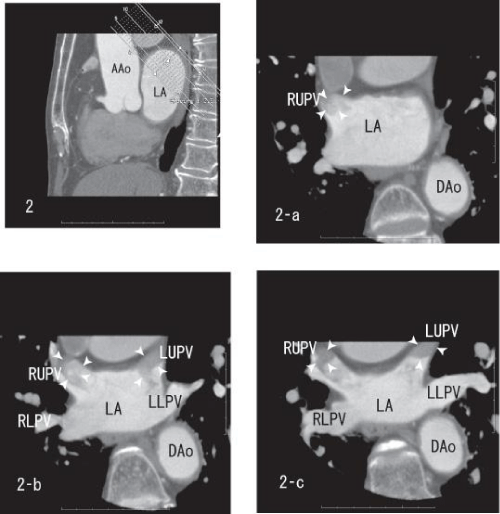

| Figure 2: Sagittal images showing thrombi within the right upper and the left upper pulmonary veins (white arrow head). The merge of thrombi was vague (2-a and 2-b). The right upper and the left upper pulmonary veins demonstrated the sharp merge of enhancement (2-c). AAo: Ascending Aorta; DAo: Descending Aorta; LA: Left Atrium; LUPV: Left Upper Pulmonary Vein; LLPV: Left Lower Pulmonary Vein; RUPV: Right Upper Pulmonary Vein; RLPV: Right Lower Pulmonary Vein. |